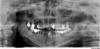

Xango Опубликовано 8 февраля, 2010 Поделиться Опубликовано 8 февраля, 2010 Здравствуйте! Помогите пожалуйста разобраться,что с моим зубом! Пролечила 2.5 месяца назад,до сих пор беспокоит боль,распирание(но не сильно) Два раза обращалась к своему врачу-делали повторные снимки,но она говорит что всё в порядке,направила на УВЧ,после которого ничего не изменилось.Что делать-не знаю,приступила к протезированию-зуб идёт под коронку,может стоит перелечить? Снимок прилагаю. Ссылка на комментарий

Fred Опубликовано 8 февраля, 2010 Поделиться Опубликовано 8 февраля, 2010 Здравствуйте! Помогите пожалуйста разобраться,что с моим зубом! Пролечила 2.5 месяца назад,до сих пор беспокоит боль,распирание(но не сильно) Два раза обращалась к своему врачу-делали повторные снимки,но она говорит что всё в порядке,направила на УВЧ,после которого ничего не изменилось.Что делать-не знаю,приступила к протезированию-зуб идёт под коронку,может стоит перелечить? Снимок прилагаю. В переднем корне канальная пломба выходит за пределы корня ...Сразу после пломбирования боль была сильнее? Ссылка на комментарий

bazishka Опубликовано 12 февраля, 2010 Поделиться Опубликовано 12 февраля, 2010 Я не пойму, а почему никто не обращает внимания на то, что корни зуба сообщаются с нижнечелюстным каналом???? А в медиальном корне материал выведен за верхушку..... Мне кажется, что материал оказывает давление на нижнечелюстной нерв, отсюда и продолжительные боли. Подобные случаи уже встречал... А Вы не чувствуете онемения со стороны причинного зуба? Ссылка на комментарий